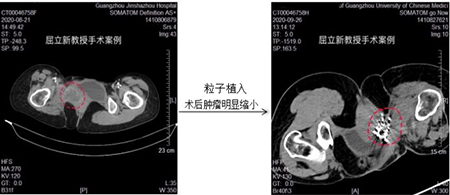

患者为女性,2年前发现“右耻骨肿瘤”于中山大学第一附属医院行“右侧耻骨、坐骨间叶源性恶性肿瘤”切除术,后进行了放疗30次化疗12次治疗。但2019年底肿瘤又转移到了鼻咽部,又行了“鼻部肿物切除术”,术后病理证实为横纹肌肉瘤,住院期间复查胸部增强CT提示双肺多发转移瘤,部分病灶累及胸膜。2020年转诊我科求医屈教授,给她进行了左肺转移肿瘤氩氦刀冷冻消融术,随后又行“动脉造影+灌注+栓塞术”,结合PD1免疫治疗,肿瘤较前明显缩小,疗效显著。

PD1鸡尾酒免疫治疗是指通过PD1免疫治疗结合微创消融治疗,粒子植入治疗,动脉介入灌注化疗等一系列微创治疗手段最大限度杀灭肿瘤,最大程度恢复肿瘤患者身体免疫机能的一系列的组合治疗。多种肉瘤如滑膜肉瘤,横纹肌肉瘤,尤文氏肉瘤,骨肉瘤和脂肪肉瘤的治疗结果表明,这种鸡尾酒疗法比传统的化疗放疗结合免疫治疗更有效,能使肿瘤显著缩小而达到延长患者生命,改善生活质量的目的。